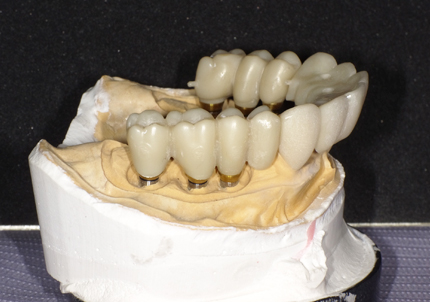

17.シリンダーテック作製(2019年10月)

側方から見て形状の確認

21.ジルコニアブリッジ試適(2020年12月)